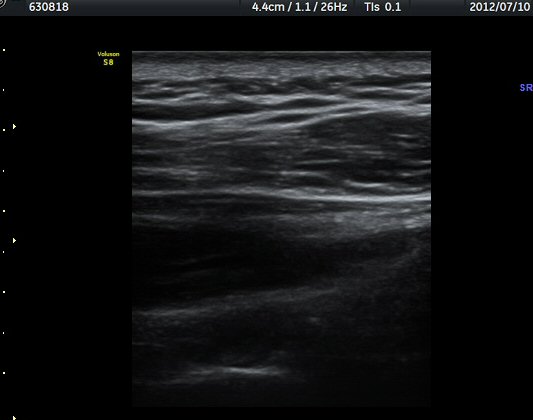

ÃÊÀ½ÆÄ °Ë»ç

¾î±ú °üÀý µÚÂÊ ÈĹæ°üÀý¼ø Ⱦ´Ü¸é°Ë»ç¿¡¼­ °üÀý¼ø ³»Ãø, °¡½Ãµ¹±â°üÀý¼ø°í¶û(spinoglenoid

notch)¿¡¼­ Àú¿¡ÄÚ ³¶Á¾ÀÌ °üÂûµÈ´Ù(±×¸² 1). ŽÃËÀÚ¸¦ À§-¾Æ·¡ ¹æÇâÀ¸·Î º¯°æÇÏ¿© °üÂûÇÒ ¶§µµ

¿ª½Ã °ß°©°ñ °¡½Ãµ¹±â(spine) ¾Æ·¡¿¡¼­ Àú¿¡ÄÚ ³¶Á¾ÀÌ °üÂûµÈ´Ù(±×¸² 2). º¼·ÏŽÃËÀÚ·Î ¹Ù²Ù¾î °ü

ÂûÇÏ´Ï  °¡½Ãµ¹±â°üÀý¼ø°í¶û¿¡¼­ Àú¿¡ÄÚ ³¶Á¾ÀÌ ´õ¿í ¶Ñ·ÈÈ÷ °üÂûµÈ´Ù(±×¸² 3, 4).